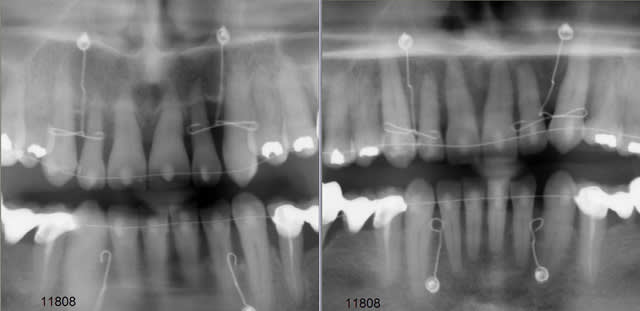

Un mouvement de version coronovestibulaire, avec la couronne qui monte, doit s'accompagner par un mouvement de racine qui part en arriere et vers le bas. De plus le changement d'axe dentaire doit donner sur le pano un raccourcicement de la dent et un eloignement de l'apex du plancher des fosses nasales. Les radios panoramiques montrent exactement le contraire!! On voit bien que l'image d'apex des incisives et des canines se rapprochent du plancher des fosses nasales malgré le changement d'axe, ce qui prouvent qu'une super ingression s'est produite reelement en plus d'une version corono-vestibulaire.

Tu veux dire la diminution du recouvrement, dans ce cas et par principe biomecanique: toute version coronovestibulaire incisive s'accompagne par une ingression relative. Donc ici nous avons la correlation de plusieurs facteurs: ingression relative due à la version, une vraie ingression incisive et peut-etre une egression des secteurs lateraux comme mouvement parasite à l'usage de l'arc continu dans un cas de supra incisive. Il est tres difficile de determiner la part de chaque element. Mais je suis certain que l'ingression incisive vraie est le facteur le plus important dans ce mouvement.

L'ingression pure au niveau des incisives inf est peut etre moins visible que sur les incisives sup, mais il ne faut oublier que la supra incisive inf etait moins importante aussi, il suffit de regarder le pano pour voir que le fil utilisé à l'arcade inferieure est mois deformé dans le plan vertical qu'à l'arcade maxillaire.